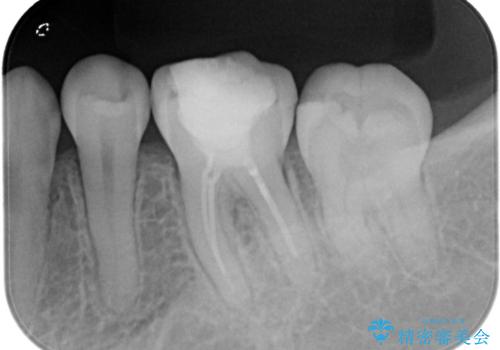

セラミッククラウンによる治療を希望されていたため根管治療から処置を行っています。

根管治療を行った歯には被せ物の治療がおすすめです。